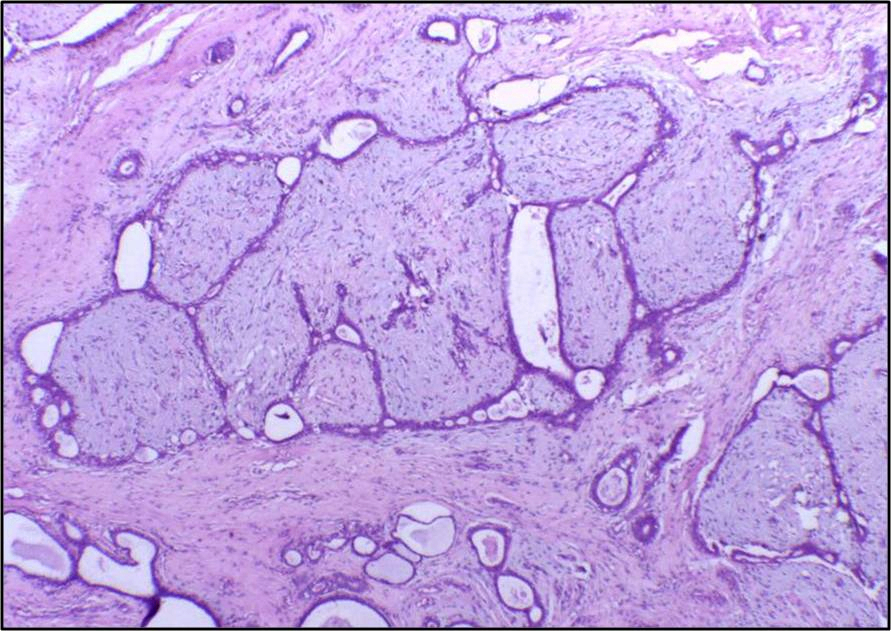

(2) 엽상종양 (phyllodes tumor)

• Intralobular stroma에서 발생하는 유방의 드문 섬유상피성 종양

- 주로 50-60대 여성에서 발생

Fibroadenoma와 유사하지만 보다 크고 성장 속도가 빠름

• 대부분 MED12 유전자 돌연변이 보유; TERT 같은 기타 유저자 변화 있는 경우 악성 가능성이 더 높음

• 촉진 시 고무 같이 단단하고 경계가 잘 구분됨

상피로 감싸진 기질이 잎 모양으로 증식함

Fibroadenoma보다 cellularity가 높고 low-grade atypia가 관찰됨

Phyllodes tumor, Wikipedia Commons